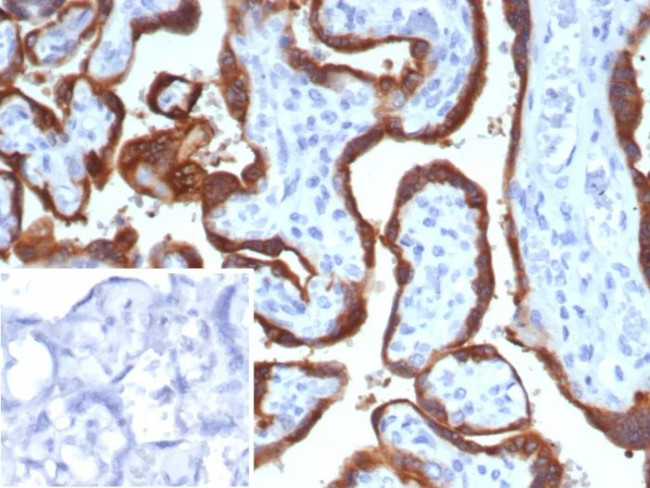

HCG-beta (Pregnancy and Choriocarcinoma Marker) Antibody in Immunohistochemistry (Paraffin) (IHC (P))

HCG-beta (Pregnancy and Choriocarcinoma Marker) Antibody (1081-MSM15-P1) in IHC (P)

Formalin-fixed, paraffin-embedded human placenta stained with HCG-beta Mouse Monoclonal Antibody (hCGa/7875). Inset: PBS instead of primary antibody; secondary only negative control. {{ $ctrl.currentElement.advancedVerification.fullName }} 验证信息 View more